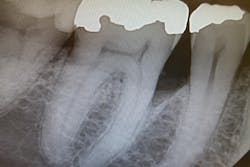

The patient in question had definitive periodontal treatment at a periodontist’s office, after which she returned to our office for routine cleanings. We noticed (after several visits) that there is a pocket remaining that is visible on the x-ray at No. 30 with calculus present at the base of the pocket. There is no bleeding, and probing reveals a 3 mm pocket. The patient started out with 4 mm to 8 mm pockets in general prior to treatment.

From the x-ray, it appears to be rather deep. [See figures 1 and 2.] Is it common or possible for tissue to reattach above the calculus level where the root surface is clean and smooth, giving the clinical appearance of a healthy area? I worked in a periodontist’s office for quite a few years and saw numerous false readings from reattached tissue versus reading the film.

This one is strange. When I view the radiograph, the accretion does not look like typical calculus. There appears to be some space under the deposit, and it is quite large. Also, there appears to be a small piece of calculus remaining on the 2015 radiograph. Since soft tissue cannot be seen on a radiograph and the probing is only 3 mm, I would guess that the tissue has closed over whatever this accretion is, or the calculus is impeding probe positioning to the base of the sulcus.

I think we are well aware that periodontal probing is often inaccurate due to problems with angulation and root accretions that block the probe from being inserted correctly. A 3 mm reading on the area you shared seems strange, to say the least.

Thank you for sharing this most interesting case. If this lady were my patient, I would want her seen by a periodontist. If she didn’t like the first one, find another one. She may need flap surgery to figure this out. I would consider it a ticking time bomb, given the strange nature of the accretion and the surrounding bone. The safe route is to have a specialist decide if this is something that warrants further treatment. It is obvious that the patient is losing bone, and if she waits, she could lose the tooth.